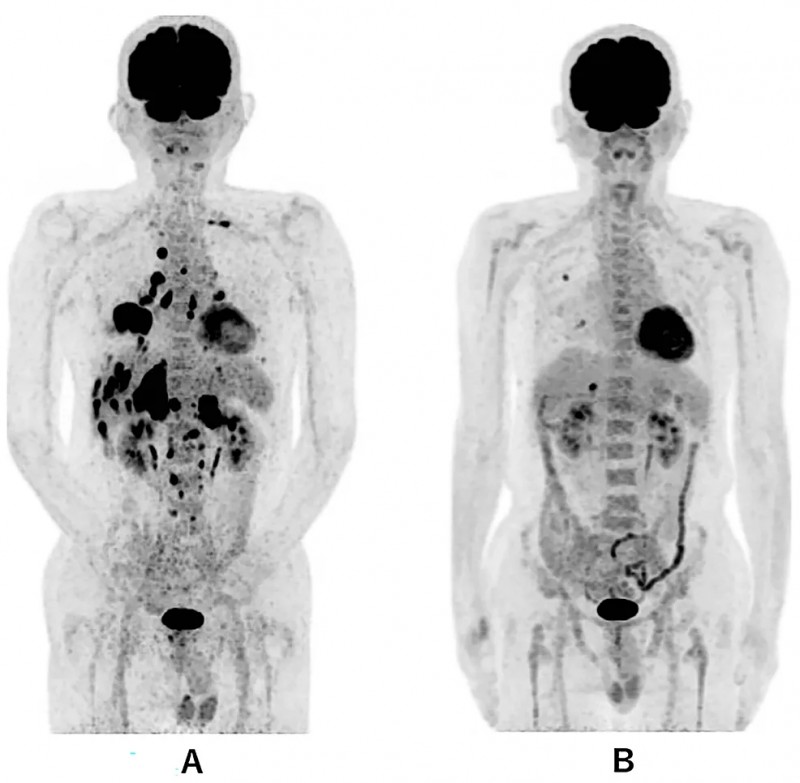

《Cureus》期刊报道了一个40岁晚期小肠癌男性患者的救治案例:该患者合并主动脉旁淋巴结转移与腹膜播散,对化疗无应答,且出现胆管、十二指肠梗阻,已接受胆管支架置入及中心静脉营养支持。因腹部癌痛剧烈,患者先接受8Gy单次姑息性调强放射治疗(IMRT),但疼痛控制不佳,体能状态(PS)评分为4分,需依赖轮椅活动。随后患者入组创新联合治疗方案:IMRT放疗3周后,启动WT1-DC疫苗+α-半乳糖神经酰胺脉冲树突状细胞(α-Galcer-DC)+纳武单抗输注治疗,同时配合两次活化淋巴细胞治疗,总疗程约3个月。

治疗效果显著:治疗前后3个月的腹部CT显示小肠癌病灶大幅减少(详见下图);血液检查提示CA19-9肿瘤标志物水平显著下降,胆红素降低,肝功能明显改善。更令人振奋的是,患者腹痛缓解,恢复流质饮食,PS评分提升至2分——无需拐杖即可步行至医院,且能自主完成如厕、洗澡等日常活动。

▼该患者接受DC免疫治疗前与治疗后的肿瘤大小对比

▲图源“Cureus”,版权归作者所有,如无意中侵犯了知识产权,请联系我们删除